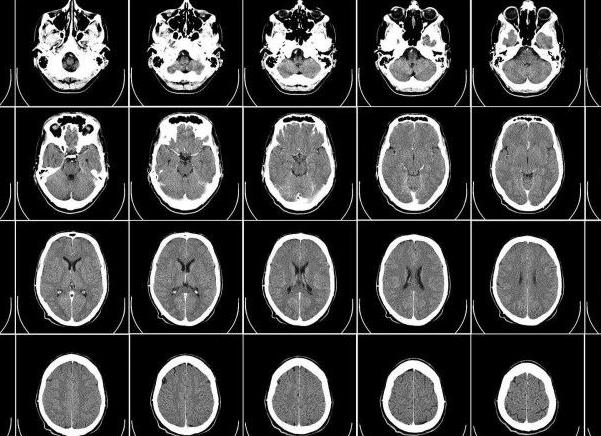

получение различных срезов при МРТ мозга

Томограф показывает орган в виде срезов. Таким образом, результат обследования – это большой лист, испещренный маленькими фотографиями каждого среза интересующего органа.

Можно задать ширину среза – например, каждые два сантиметра. Очень хорошо различаются и ткани. То есть врач сразу поймет, с чем имеет дело: жировой прослойкой, осколком кости или полостью, заполненной жидкостью.